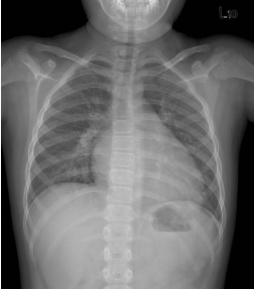

30 一位 4 歲女孩因久咳不癒,來院就診,身體檢查發現心跳約 96 次/分,呼吸稍快,肝臟在右肋 骨下 2 公分處還可摸到,心臟聽診不太清楚,胸部 X 光片如附圖。由這 X 光片可看到何種最主 要異常的變化?

(A)肺癌的變化 (B)心臟擴大 (C)氣胸 (D)橫膈膜向上移動